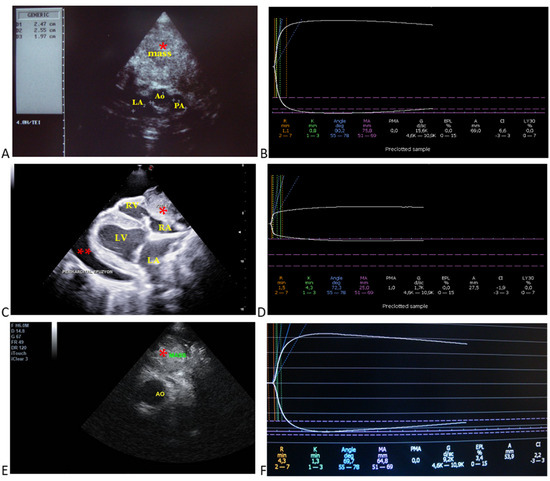

3.3. Echocardiographic Findings

3.4. Diagnostic Imaging and Cytological Findings